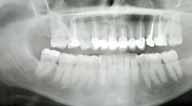

The Dental Panoramic Tomogram (DPT) confirmed the presence of all permanent teeth including the developing third molars (Figure 3). Root morphology appeared normal. The upper right central incisor had a root canal filling. The upper standard occlusal

radiograph revealed that the upper right central incisor had an adequate root filling with no periapical area. In the cephalometric assessment (Figure 4), the ANB value of 7° suggested a moderate Class II skeletal pattern. The vertical proportions were within normal values. The upper incisors were proclined at 122° and the lower incisors were of average inclination at 94°. The interincisal angle was reduced at 119°. The lower incisor to APo and the lower lip to E line were within normal limits.